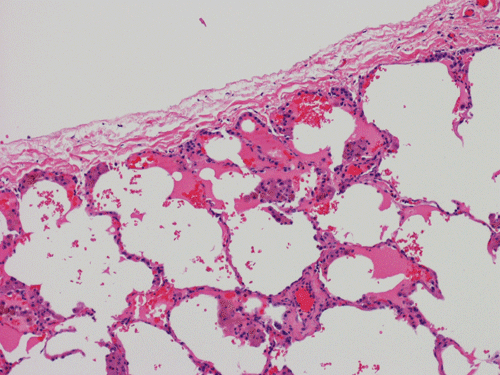

At scanning magnification (Panel A), the lung parenchyma is replaced by some coalescing fibrous nodules. The degree of involvement is variable at different fragments (Panel B and C). In the less affected areas, there are some fibrotic thickening of the septa (Panel C). In some areas, the changes are minimal and the pleural appear to be uninvolved (Panel D and E). In low to medium magnifications, these nodules of fibrosis contains a large number of hemosiderin laden macrophages (Panel F and G) admixed with fibrous tissue. The diagnostic tissue, however, is present in areas with increased cellularity. In these areas, there is a background of cells with a moderate amount of cytoplasm and bland nuclei. Some of these nuclei have kidney shape (arrow in Panel H). In some areas, many of the nuclei have a deep nuclear groove that resemble a coffee bean (arrow in Panel I). In the third type of areas, the nuclear grooving is not distinct (Panel J). Prominent eosinophilic infiltrations are almost always present. Immunohistochemistry on CD1a revealed many positive cells (Panel L). Also present in the specimen are multiple small blood vessels with thickened intima (Panel K). A Movat pentachrome stain demonstrates an internal elastic layer in these vessels and confirms that these are arteries (Panel M and N).

In the early stage of PLCH, there are interstitial infiltrates composed of LCs, lymphocytes, macrophages, eosinophils, plasma cells and fibroblasts 4. The infiltrates enlarge to form nodules centered on the small airways. Brown pigmented macrophages (smokers macrophages) are present in and around the nodules. Eosinophils tend to localize at the innermost layer of the nodules, where LCs can be most easily found in the thickened interstitium. Associated patchy interstitial and airspace organization or respiratory bronchiolitis may be present. Other smoking related changes are also common. Cavitation often occurs within the nodules which represents either an airway remenant or de novo cavitation as the inflammatory infiltrate enlarges. There is centripetal replacement of the nodules by fibroblasts which produce the classic stellate lesions of PLCH. As the disease progresses, the number of nodules, cavitary granulomas and fibrotic scars increase in number.

In the end stage, the exhausted lesions are predominantly fibrotic and largely depleted of LCs. In some regions, the fibrosis may surround cystic spaces of variable diameter to form large areas of honeycombing. This is especially predominant in the upper lobes. In cases where parenchymal scaring is present, the pulmonary function will be largely compromised. At this stage, both pulmonary function tests and radiologic findings may suggest diffuse lung disease, but biopsy will show stellate fibrotic lesions centered on the terminal airways with no identifiable interstitial inflammation. Pulmonary vasculopathy (in areas of lung remote from parenchymal nodules) is also seen in late stage PLCH. Vasculopathy manifests as intimal fibrosis, medial hypertrophy or luminal obliteration involving both venules and arteries. This may account for pulmonary hypertension seen late in PLCH.